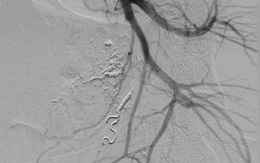

90 phút "đấu trí" với tử thần: Lần đầu tiên tại Việt Nam can thiệp thành công ca tổn thương động mạch trực tràng hiếm gặp

19/06/2021 23:59

BV Bạch Mai thông tin ca lâm sàng hiếm gặp, lần đầu tiên được can thiệp thành công tại Việt Nam. Sau 90 phút "đấu trí" với tử thần, các bác sĩ đã giành lại sự sống từ lưỡi hái tử thần cho sản phụ 33 tuổi.